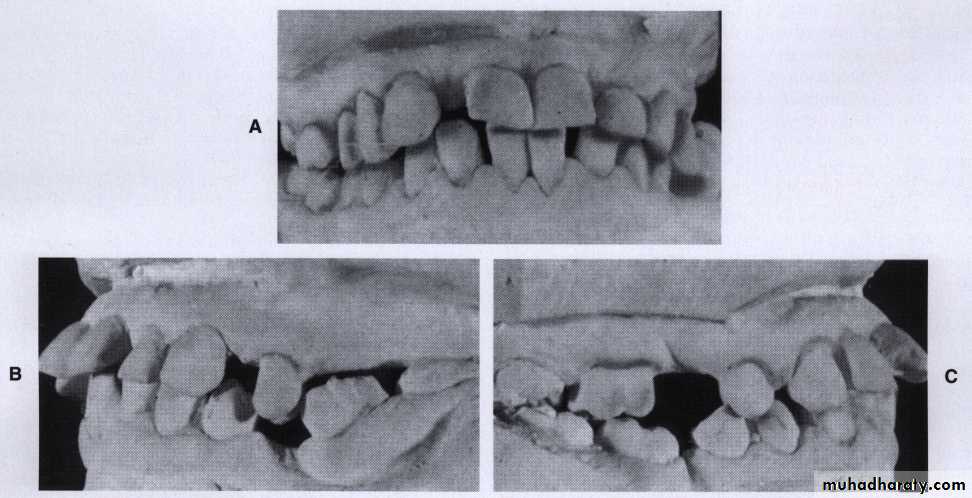

Unreplaced missing teeth

If the lower 6 has been missed & not replacedThere will be mesial drifting & tilting of lower 7& 8 with the extrusion of upper 6.

Distal cusps of lower 7are elevated & act as plunger cusp between extruded upper 6 & 7.

Distal drifting of lower 5 will open contact between premolars that led to food impaction & pocket formation.Extraction of impacted third molar